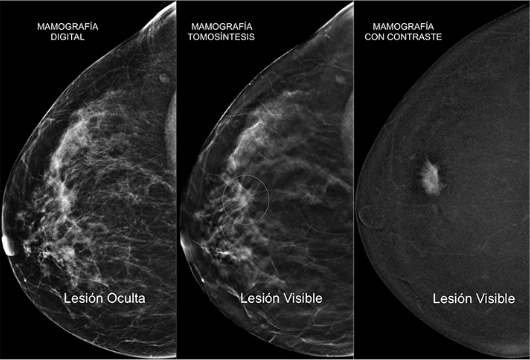

Mamografía con contraste

Recientemente, a la mamografía con tomosíntesis se ha incorporado una nueva técnica, la mamografía con contraste. Para llevarla a cabo, se inyecta a la paciente un contraste yodado (el mismo que se emplea en las pruebas de escáner) para posteriormente realizar la mamografía. Este contraste será captado por los tumores mamarios y representado en la imagen como una bombilla encendida en una habitación oscura.

Permite un incremento en la sensibilidad y especificidad de la prueba, ayudando a la detección de lesiones ocultas al aportar una información funcional y es especialmente útil en pacientes con mamas densas.

Podrá ser en ciertos casos una alternativa/complemento de la Resonancia Magnética de Mama.